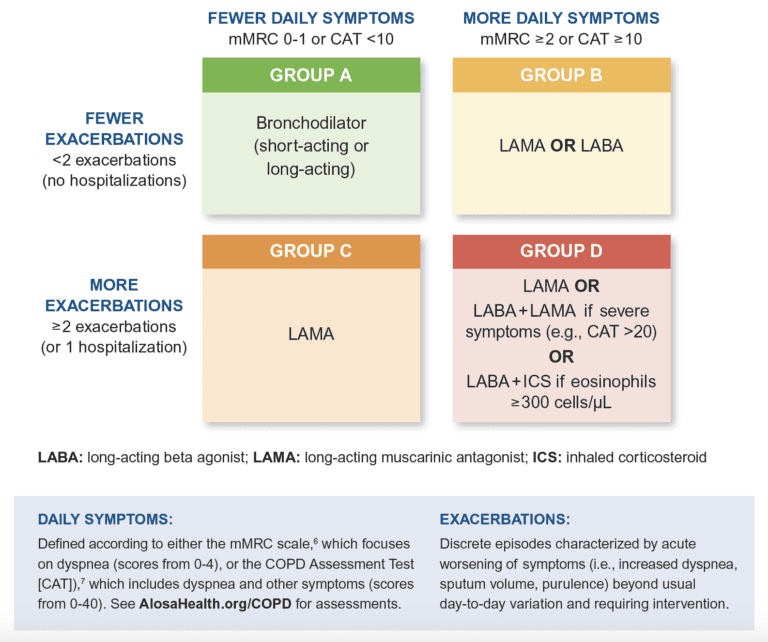

Gold Classification 2024 – Carina Starlin

beckieqgilbertine.pages.dev

Copd Gold Guidelines 2019 – AverytaroRose

averytarorose.blogspot.com

Gold classification 2024. Copd triple therapy treatment fda approved breztri & trelegy. Inhaler astrazeneca